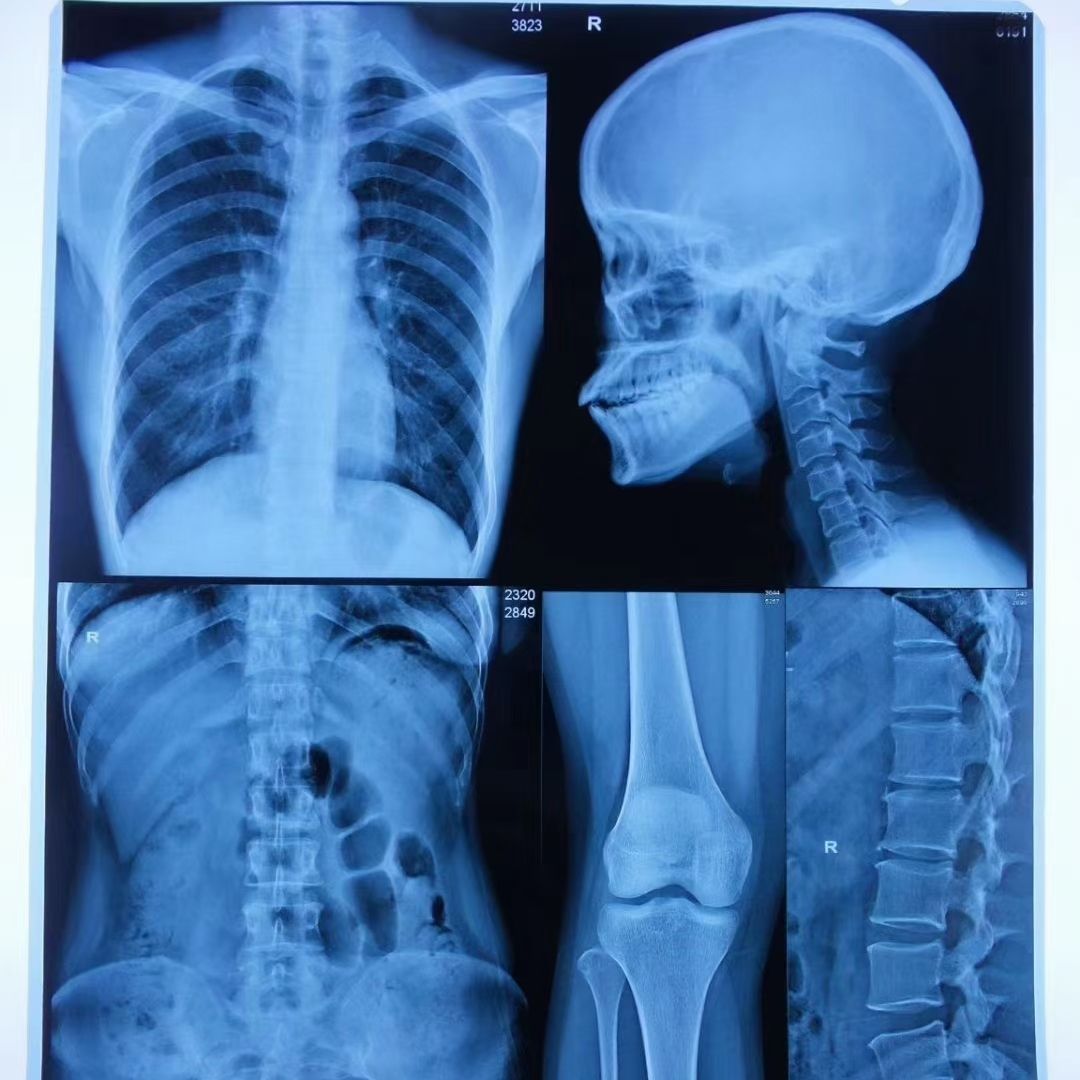

Medical X Ray Dry Thermal Printer Films

- Product description: medical films, thermal films, X-ray films, good quality medical films, dry films for medical use

PRODUCT INTRODUCTION

This dry films designed especially for Dry Laser Images with blue color for ultrasound Dept. and radiology Dept. of hospital. This new film is laser processed and does not require wet processing chemistry, can accurately through the computer processing of all kinds of medical imaging, get rid of the traditional silver halide product show fixing bath processing program, eliminate the flushing processing waste liquid pollution to the environment. It's Compatible FUJI XEROX 5005D and OKI941 printer.